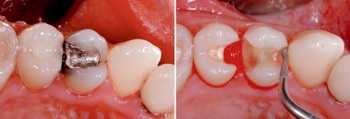

В зависимости от поставленной задачи по исправлению дефекта стоматологи используют различные методы реставрации зубов. При незначительном разрушении восстановить зуб можно непосредственно во рту пациента: такой метод носит название прямой реставрации. В качестве материалов для реставрации зубов прямым методом применяются различные по составу цементы и композиты, особой популярностью среди которых пользуются фотополимеры (гелиокомпозиты) - пластичные материалы, приобретающие твердость после воздействия светом стоматологической лампы.

Но при сильных разрушениях прямая реставрация зубов фотополимерами не обеспечивает зубу нужной устойчивости к жевательным нагрузкам, и более эффективным является непрямой метод реставрации.

Но при сильных разрушениях прямая реставрация зубов фотополимерами не обеспечивает зубу нужной устойчивости к жевательным нагрузкам, и более эффективным является непрямой метод реставрации.

РЕСТАВРАЦИЯ ЗУБОВ КЕРАМИЧЕСКИМИ ВКЛАДКАМИ

РЕСТАВРАЦИЯ ЗУБОВ КЕРАМИЧЕСКИМИ ВКЛАДКАМИПри прямой реставрации элемент, повторяющий недостающую часть зуба (так называемая вкладка, винир), изготавливается в лаборатории по индивидуальному слепку. В терапевтической и эстетической стоматологии реставрация зубов вкладками и винирами является хорошей альтернативой традиционным коронкам.

Если вкратце обрисовать основные этапы реставрации зубов композитами, среди них следует выделить: диагностику, то есть определение анатомических особенностей, структуры и цвета зубов пациента; подбор материалов, обеспечивающих желаемый результат реставрации; подготовку поверхности зуба и собственно реставрацию. В настоящее время наиболее распространенной считается многослойная техника реставрации зубов, для выполнения которой используются разнообразные виды композитных материалов. В сравнении с протезированием коронками, композитная реставрация зубов на форумах стоматологов обычно получает больше положительных отзывов: данная техника не только позволяет сократить сроки и стоимость лечения, но и является щадящей по отношению к тканям зуба. Особенно актуален такой метод при реставрации переднего зуба – за одно посещение стоматолога можно полностью преобразить внешний вид и эстетику зубов.

ЭТАПЫ РЕСТАВРАЦИИ ЗУБОВ ФОТОКОМПОЗИТОМ